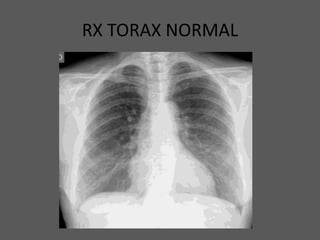

RX TORAX NORMAL